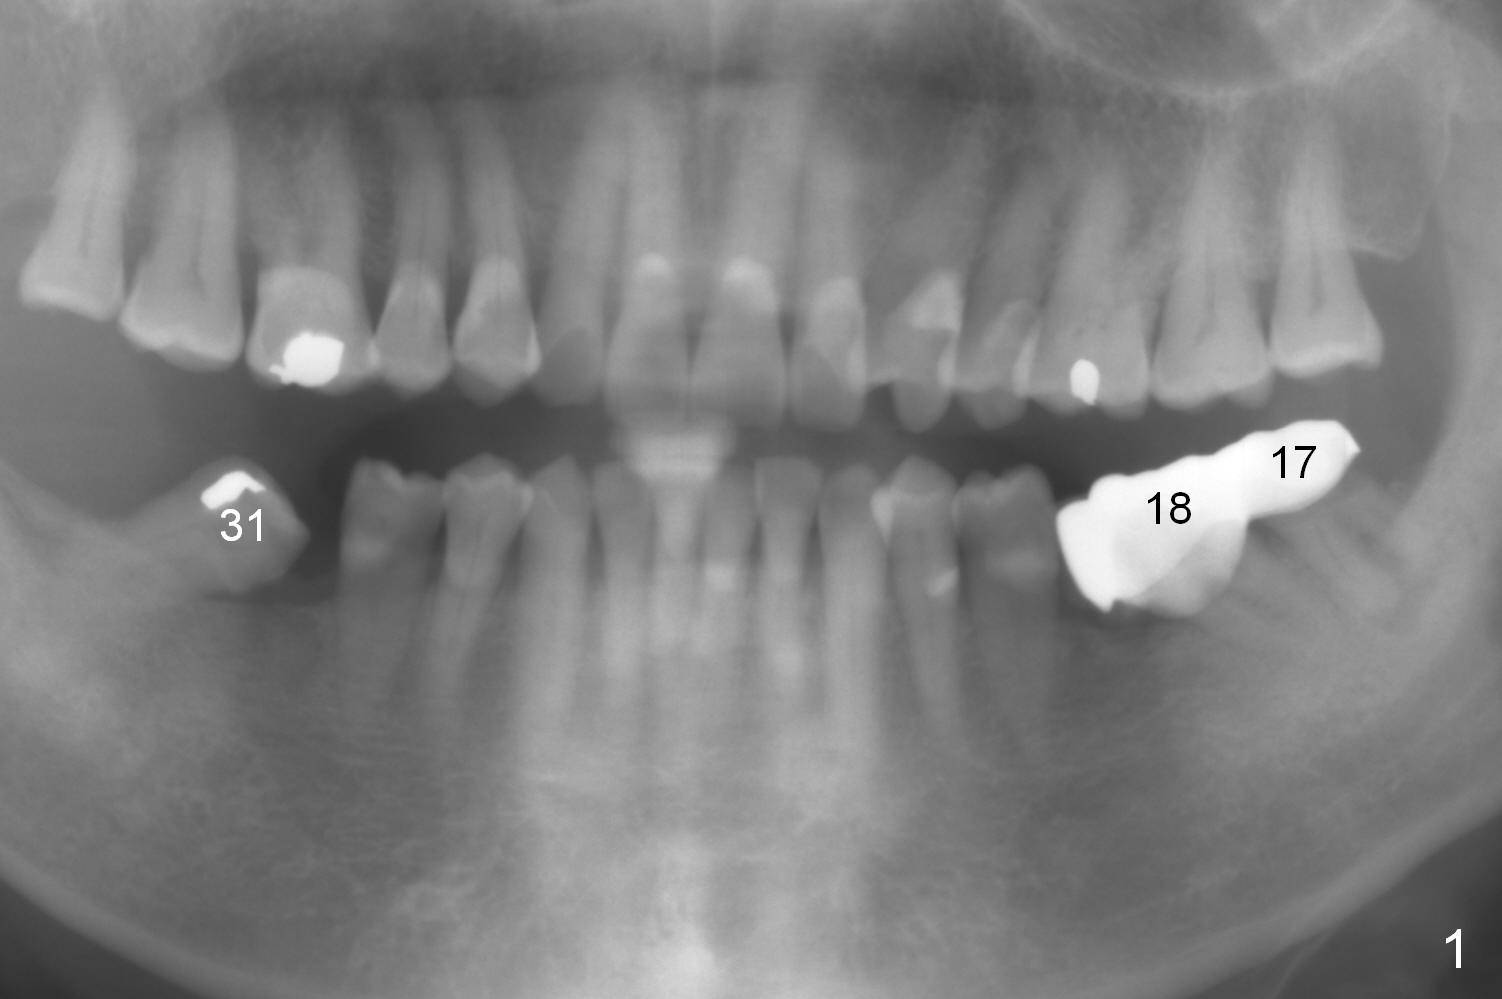

A 82-year-old man has pain in the lower left bridge. There is a buccal apical fistula associated with the tooth #17 (Fig.1). An immediate implant will be placed at #17 after bridge removal (Fig.2,3 blue). Once it osteointegrates, it will be used an anchorage (direct (instead of indirect), most efficient) to upright the tooth #18 (change the longitudinal axis from red line to purple one (Fig.4); white circle: center of resistance (rotation)). Then an implant will be placed at #19 (white rectangle).